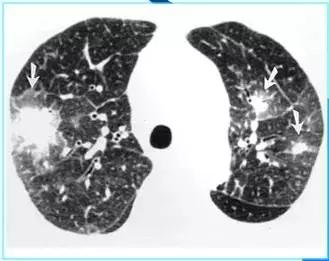

CT征象一:树芽征

由终末细支气管和肺泡腔内病变形成的小结节影与分支细线影构成的酷似春天的树枝发芽状,称“树芽征”(tree-in-bud)

CT表现:多在肺外围支气管末梢呈2-4mm大小结节与树枝状的高密度影。

意义:多表明有小气道病变如:细支气管炎症、弥漫泛发性细支气管炎及肺结核病灶或播散等

末梢细支气管扩张形成粘液栓——酷似“树芽征”

末梢细支气管与肺泡结核灶及播散——酷似“树芽征”

“树芽征”:活动性肺结核支气管播散;泛细支气管炎